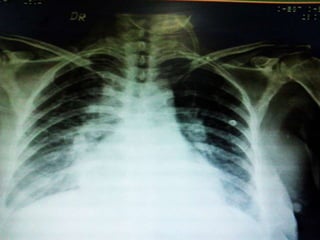

Chest Xray showed Flash Pulmonary Edema

and patient started having cough with

productive sputum with blood tinge and used

to become breathless on and off

• On 27thJan Patient became breathless and started desaturating so she was shifted to MICU and was intubated and managed as Acute Coronary syndrome as Trop T was 116.2 and CPK MB was 9.96. Pro BNP was 7868. Patient was started on antiplatelets and anticoagulants. Then patient was extubated on 28th Jan. Chest Xray showed Flash Pulmonary Edema and patient started having cough with productive sputum with blood tinge and used to become breathless on and off